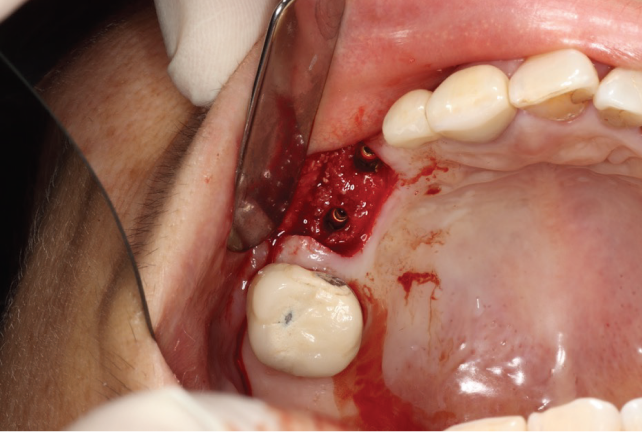

Lecture Topic

The first day will focus on pre-extraction site evaluation, dental implant planning, and site preservation procedures to ensure a smooth path towards surgical implant placement. The second day will focus on simple strategies for guided bone regeneration when there is a horizontal ridge deficiency.

Techniques for staged and simultaneous guided bone regeneration with implant placements will taught. Techniques utilising autologous bone, allografts, xenografts and alloplasts will be covered in depth.

The course will introduce the use of autologous blood concentrates such as PRF and CGF in regeneration procedures. Different membranes and their indications such as collagen and Ti-reinforced PTFE will also

be covered.

Day 1

Lecture & Hands-on

4

Post extraction site cleaning

and disinfection

and disinfection